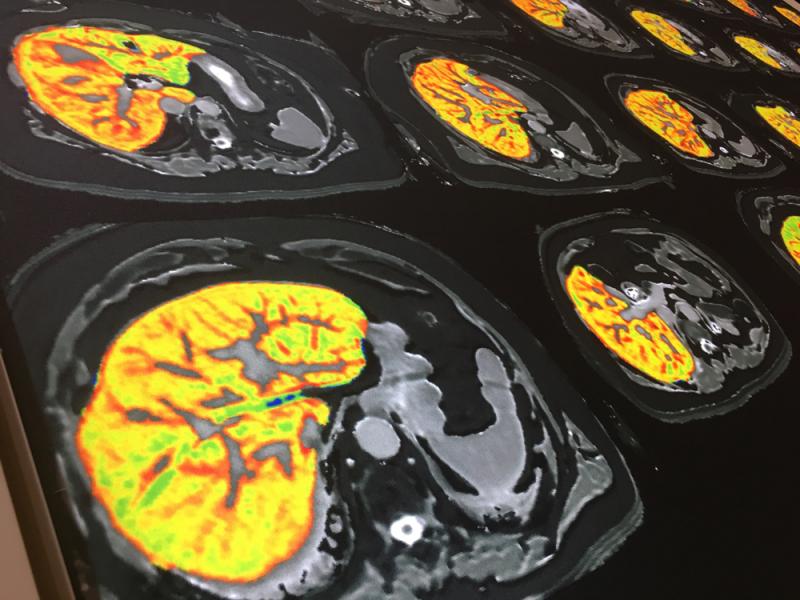

Here are images of some of the newest new medical imaging technologies displayed on the expo floor at the Radiological Society of North America (RSNA) 2019 meeting. Use the slider images below to see the photos.